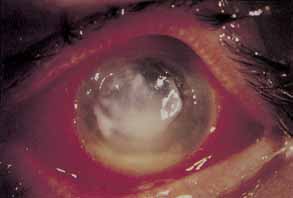

BACTERIAL KERATITIS

Infectious keratitis is the single most feared complication of contact lens wear.138 Corneal infections may range from small peripheral ulcers to large suppurative central ulcers. Infectious ulcers must be differentiated from sterile ulcers, particularly in association with disposable extended lens wear. Bacterial keratitis occurs most frequently in association with extended soft contact lens wear and least frequently among rigid PMMA wearers. Bacterial keratitis is by far the most frequent form of infectious keratitis associated with contact lens wear, with Pseudomonas aeruginosa being the most frequent isolate (Fig. 5). In most cases of infectious keratitis, there is an identifiable breach of contact lens care protocol that predisposes the patient to infection. It is imperative to make a swift and accurate diagnosis of infectious keratitis and to initiate appropriate topical antibiotic therapy to minimize visual loss secondary to stromal scarring.

Fig. 5 Central Pseudomonas keratitis with hypopyon.